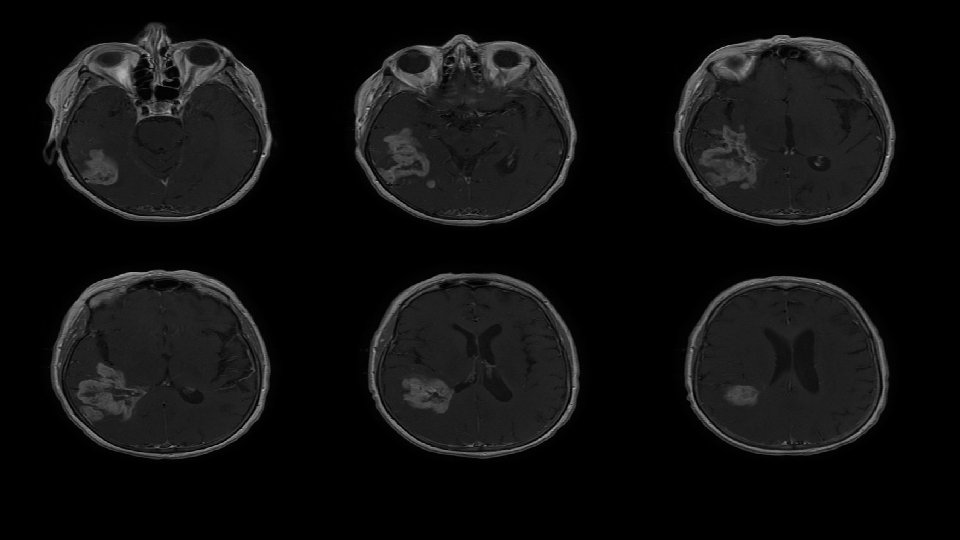

GROSS TOTAL RESECTION (GTR)

Glioblastoma always recurs December 2010 March 2011